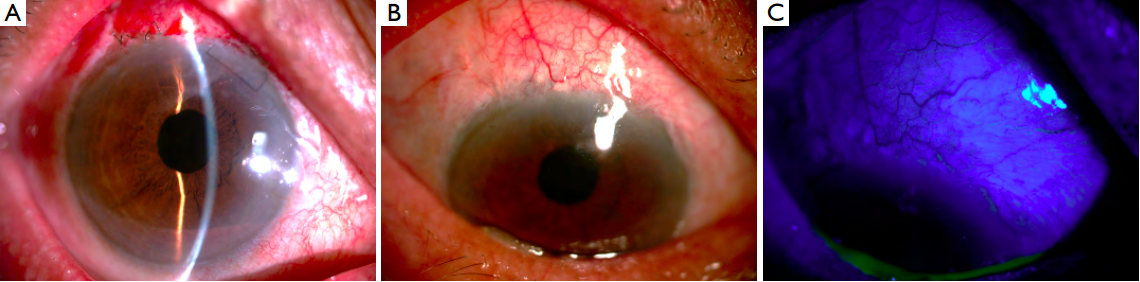

glaucoma medications. Slit-lamp examination revealed a

large avascular filtration bleb overhanging on the cornea

with a thin base connected to the conjunctiva (Figure 1A,B).

No leakage from the filtration bleb could be detected

(Figure 1C). Ultrasound biomicroscopy (UBM) confirmed

Figure 1 Slit-lamp examination revealed a large avascular filtration bleb overhanging on the cornea

(A) with a thin base connected to the

conjunctiva (B). No leakage could be seen (C). Black arrow: thin base connected to the conjunctiva.